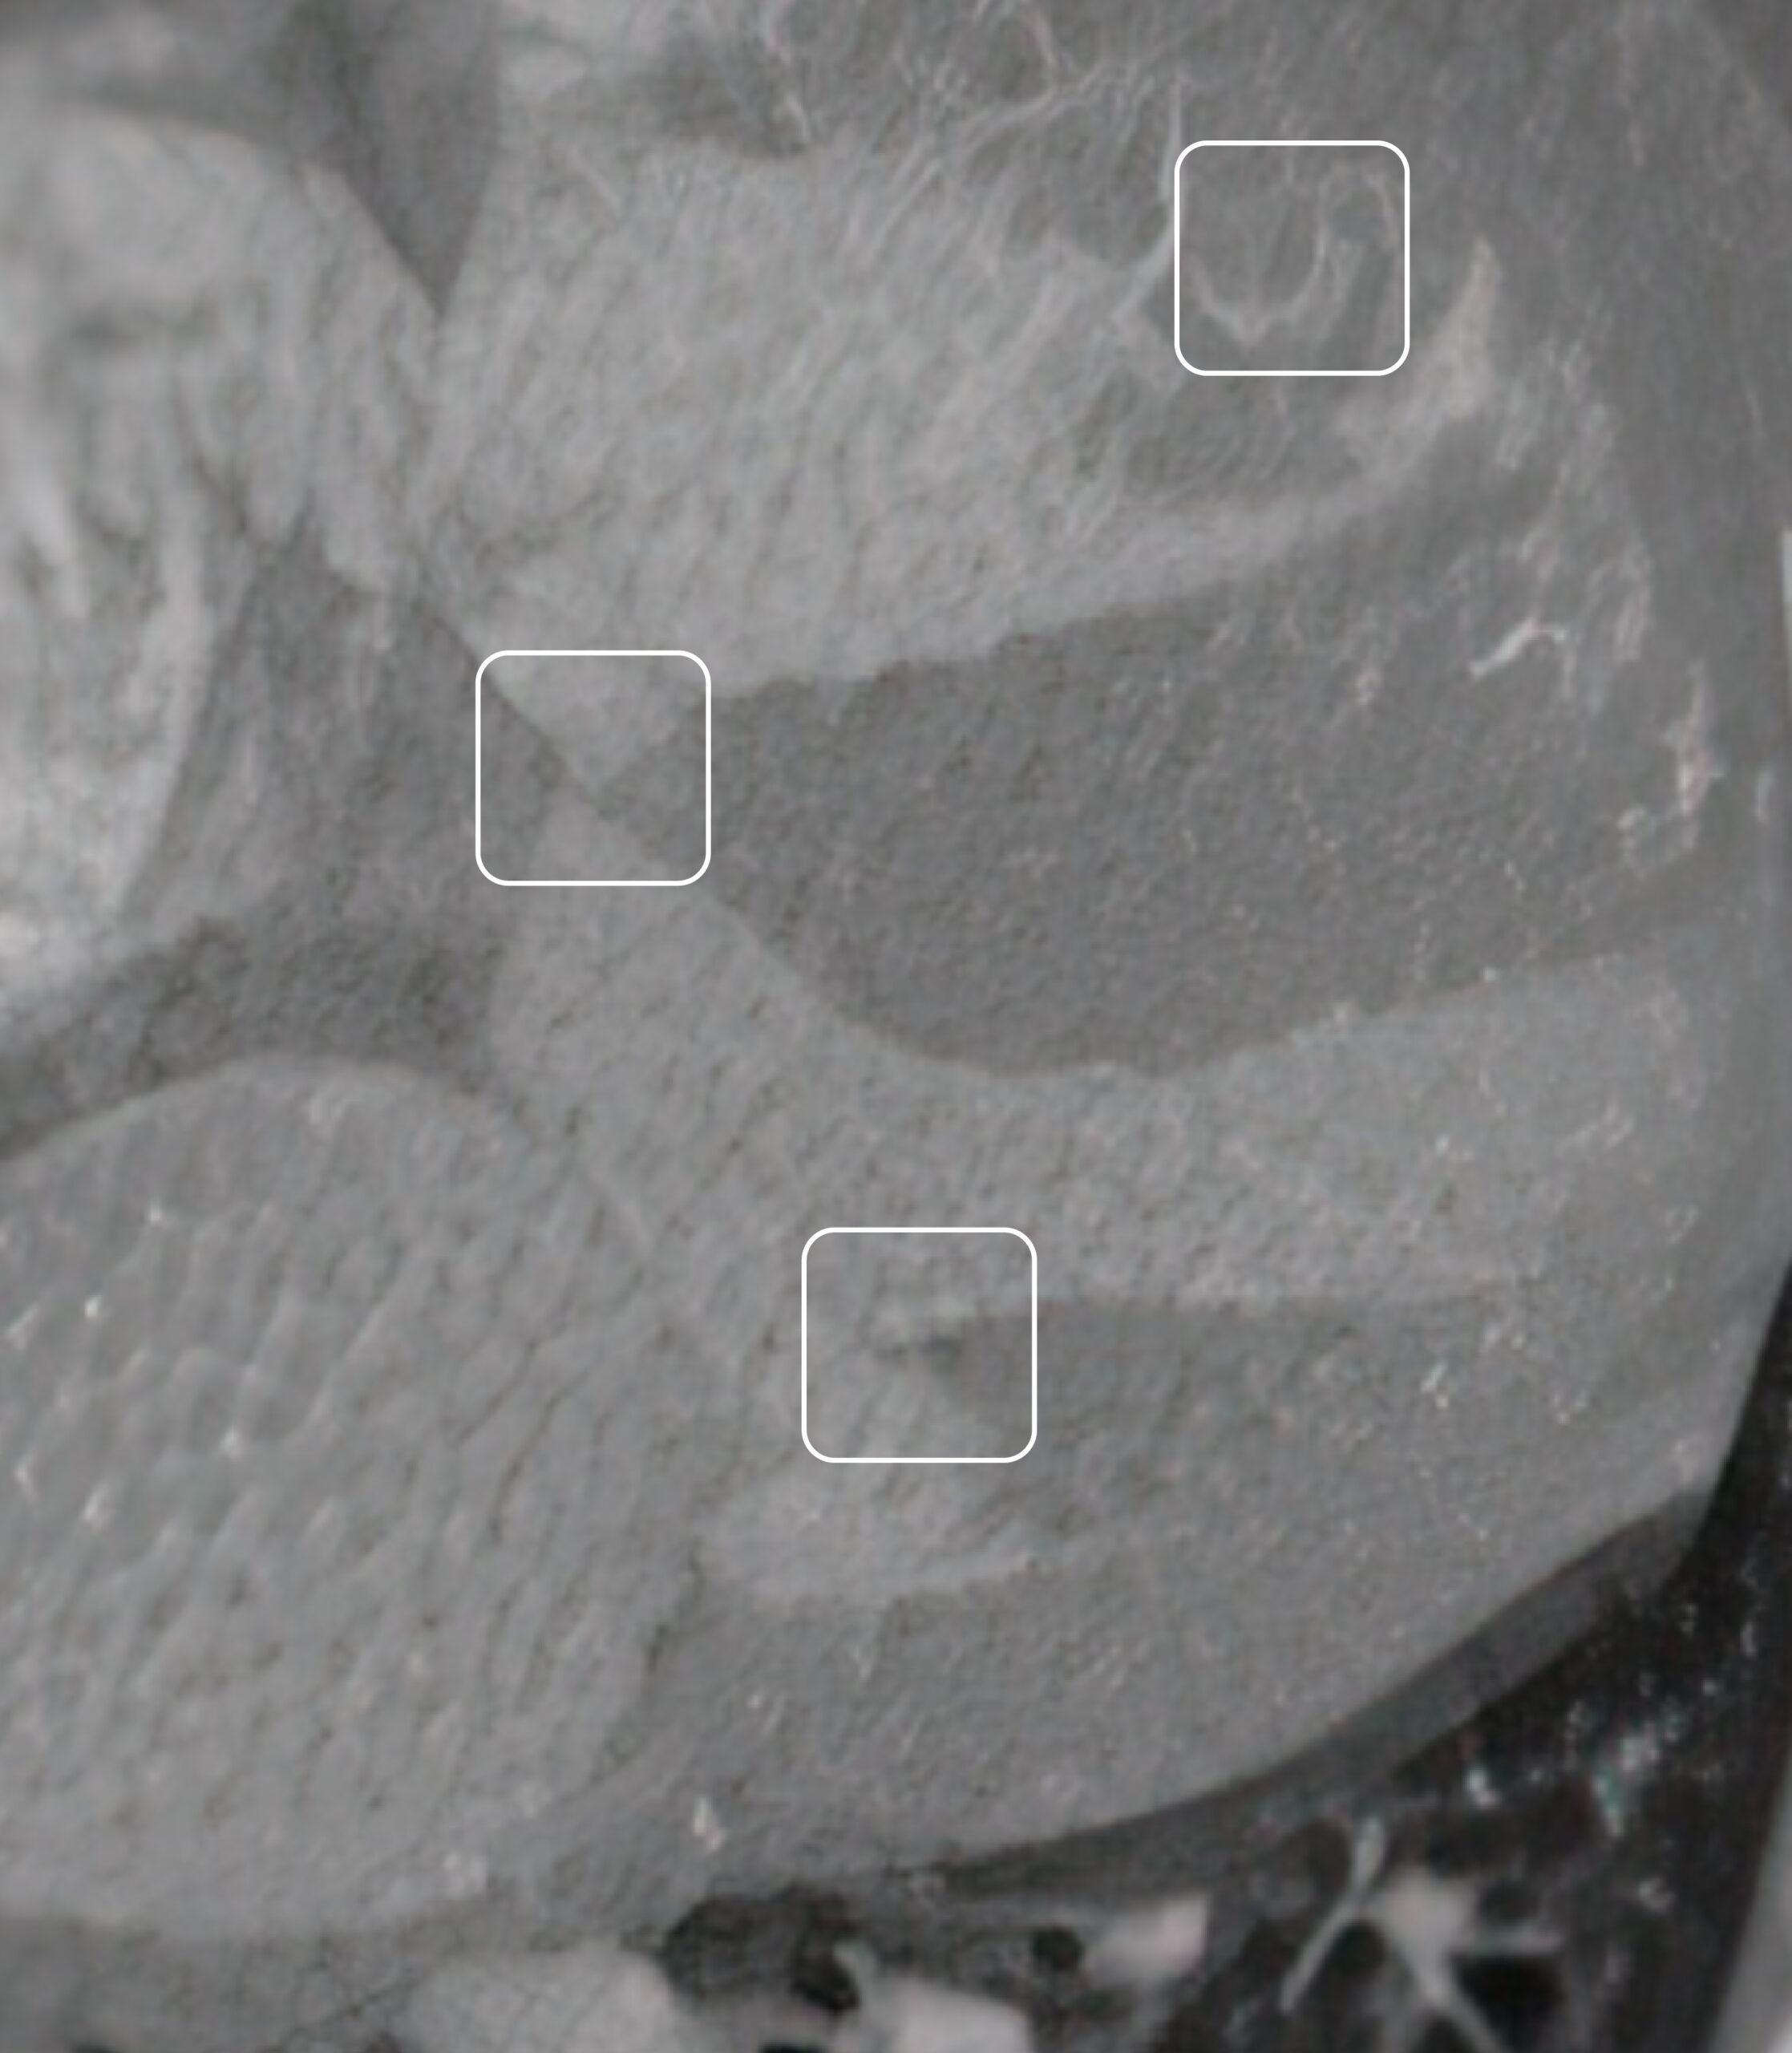

La integración de algoritmos de aprendizaje profundo permite identificar biomarcadores y anomalías tisulares que suelen ser imperceptibles en la radiología convencional. Al analizar la densidad y la textura del dato médico a nivel de píxel, nuestra tecnología facilita la detección precoz de patologías críticas y tumoraciones en estadios iniciales.

Nuestra tecnología de inteligencia artificial analiza patrones microscópicos y biomarcadores imperceptibles al ojo humano en las fases iniciales de una patología. Gracias a nuestros análisis y algoritmos de alta sensibilidad, logramos identificar anomalías y tumoraciones en estadios tempranos, permitiendo una intervención preventiva que mejora drásticamente el pronóstico del paciente y la viabilidad de los tratamientos.

Nuestros algoritmos analizan el dato médico (TAC/RM) a nivel de píxel, identificando variaciones de densidad y texturas (radiómica) que pueden ser imperceptibles para el ojo humano. Esto permite detectar anomalías en estadios muy tempranos.

Es la extracción de grandes cantidades de datos cuantitativos de las imágenes médicas. La IA utiliza estos datos para encontrar patrones que relacionan la imagen con la biología de la patología, algo que va mucho más allá de la simple visualización.